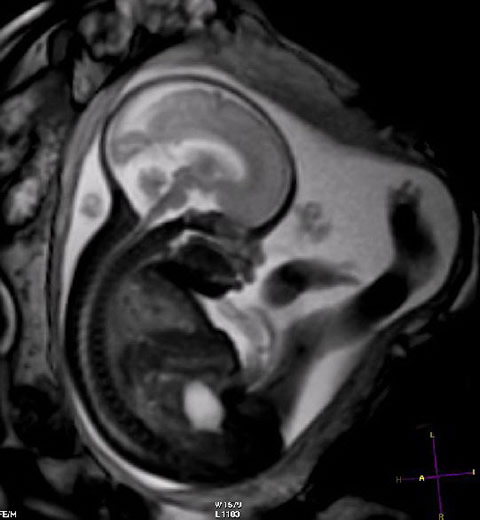

Resonancia magnética: no se detectaron efectos adversos en el primer trimestre del embarazo

07 septiembre 2016

Sin embargo, el uso de medios de contraste con gadolinio en cualquier trimestre se asoció con un aumento de complicaciones durante y después del embarazo. JAMA, 6 de septiembre de 2016